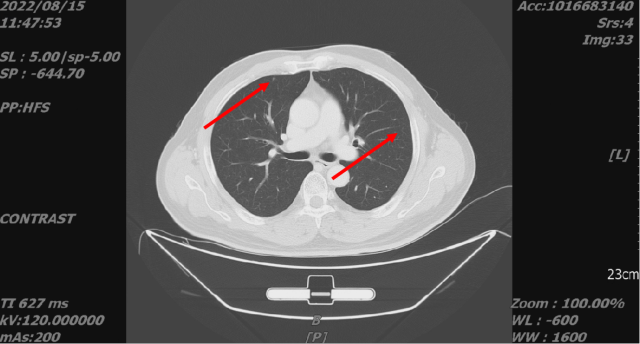

舒尼替尼治疗后,2022-08-15 复查 CT

1. 结合临床,左肾癌治疗后,较前片 2022-5-20 好转;左侧肾上腺受累;考虑肝转移,较前缩小或显示不清。

2. 双肺转移,较前好转。

2022-08-15 CT